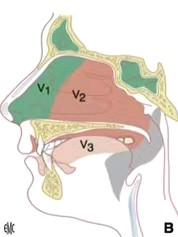

三叉神经是第Ⅴ对颅神经,为混合神经,含有感觉纤维(一般躯体传入纤维)和运动纤维(特殊内脏传出纤维)。其中,感觉纤维占大部分,胞体位于三叉神经节内,其周围突形成三叉神经的3个分支:眼神经、上颌神经与下颌神经,分别经眶上裂、圆孔与卵圆孔出颅腔。

三叉神经